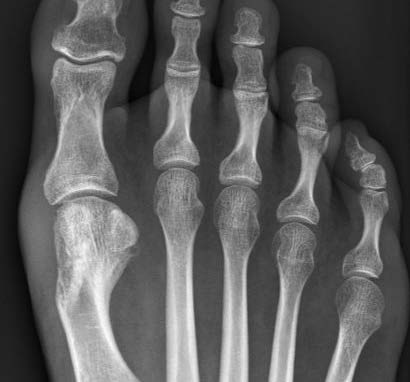

6 Monate postoperativ

Guter Ein- und Umbau der Knochenschraube - Transplantat nur mehr rudimentär sichtbar.